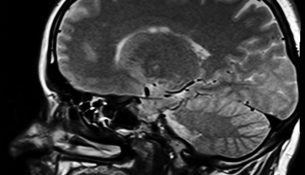

Es gibt eine Vielzahl an Erkrankungen, die eine Operation am Kopf notwendig machen. Gehirntumore oder Aussackungen von Hirnarterien (Aneurysmen) erfordern…